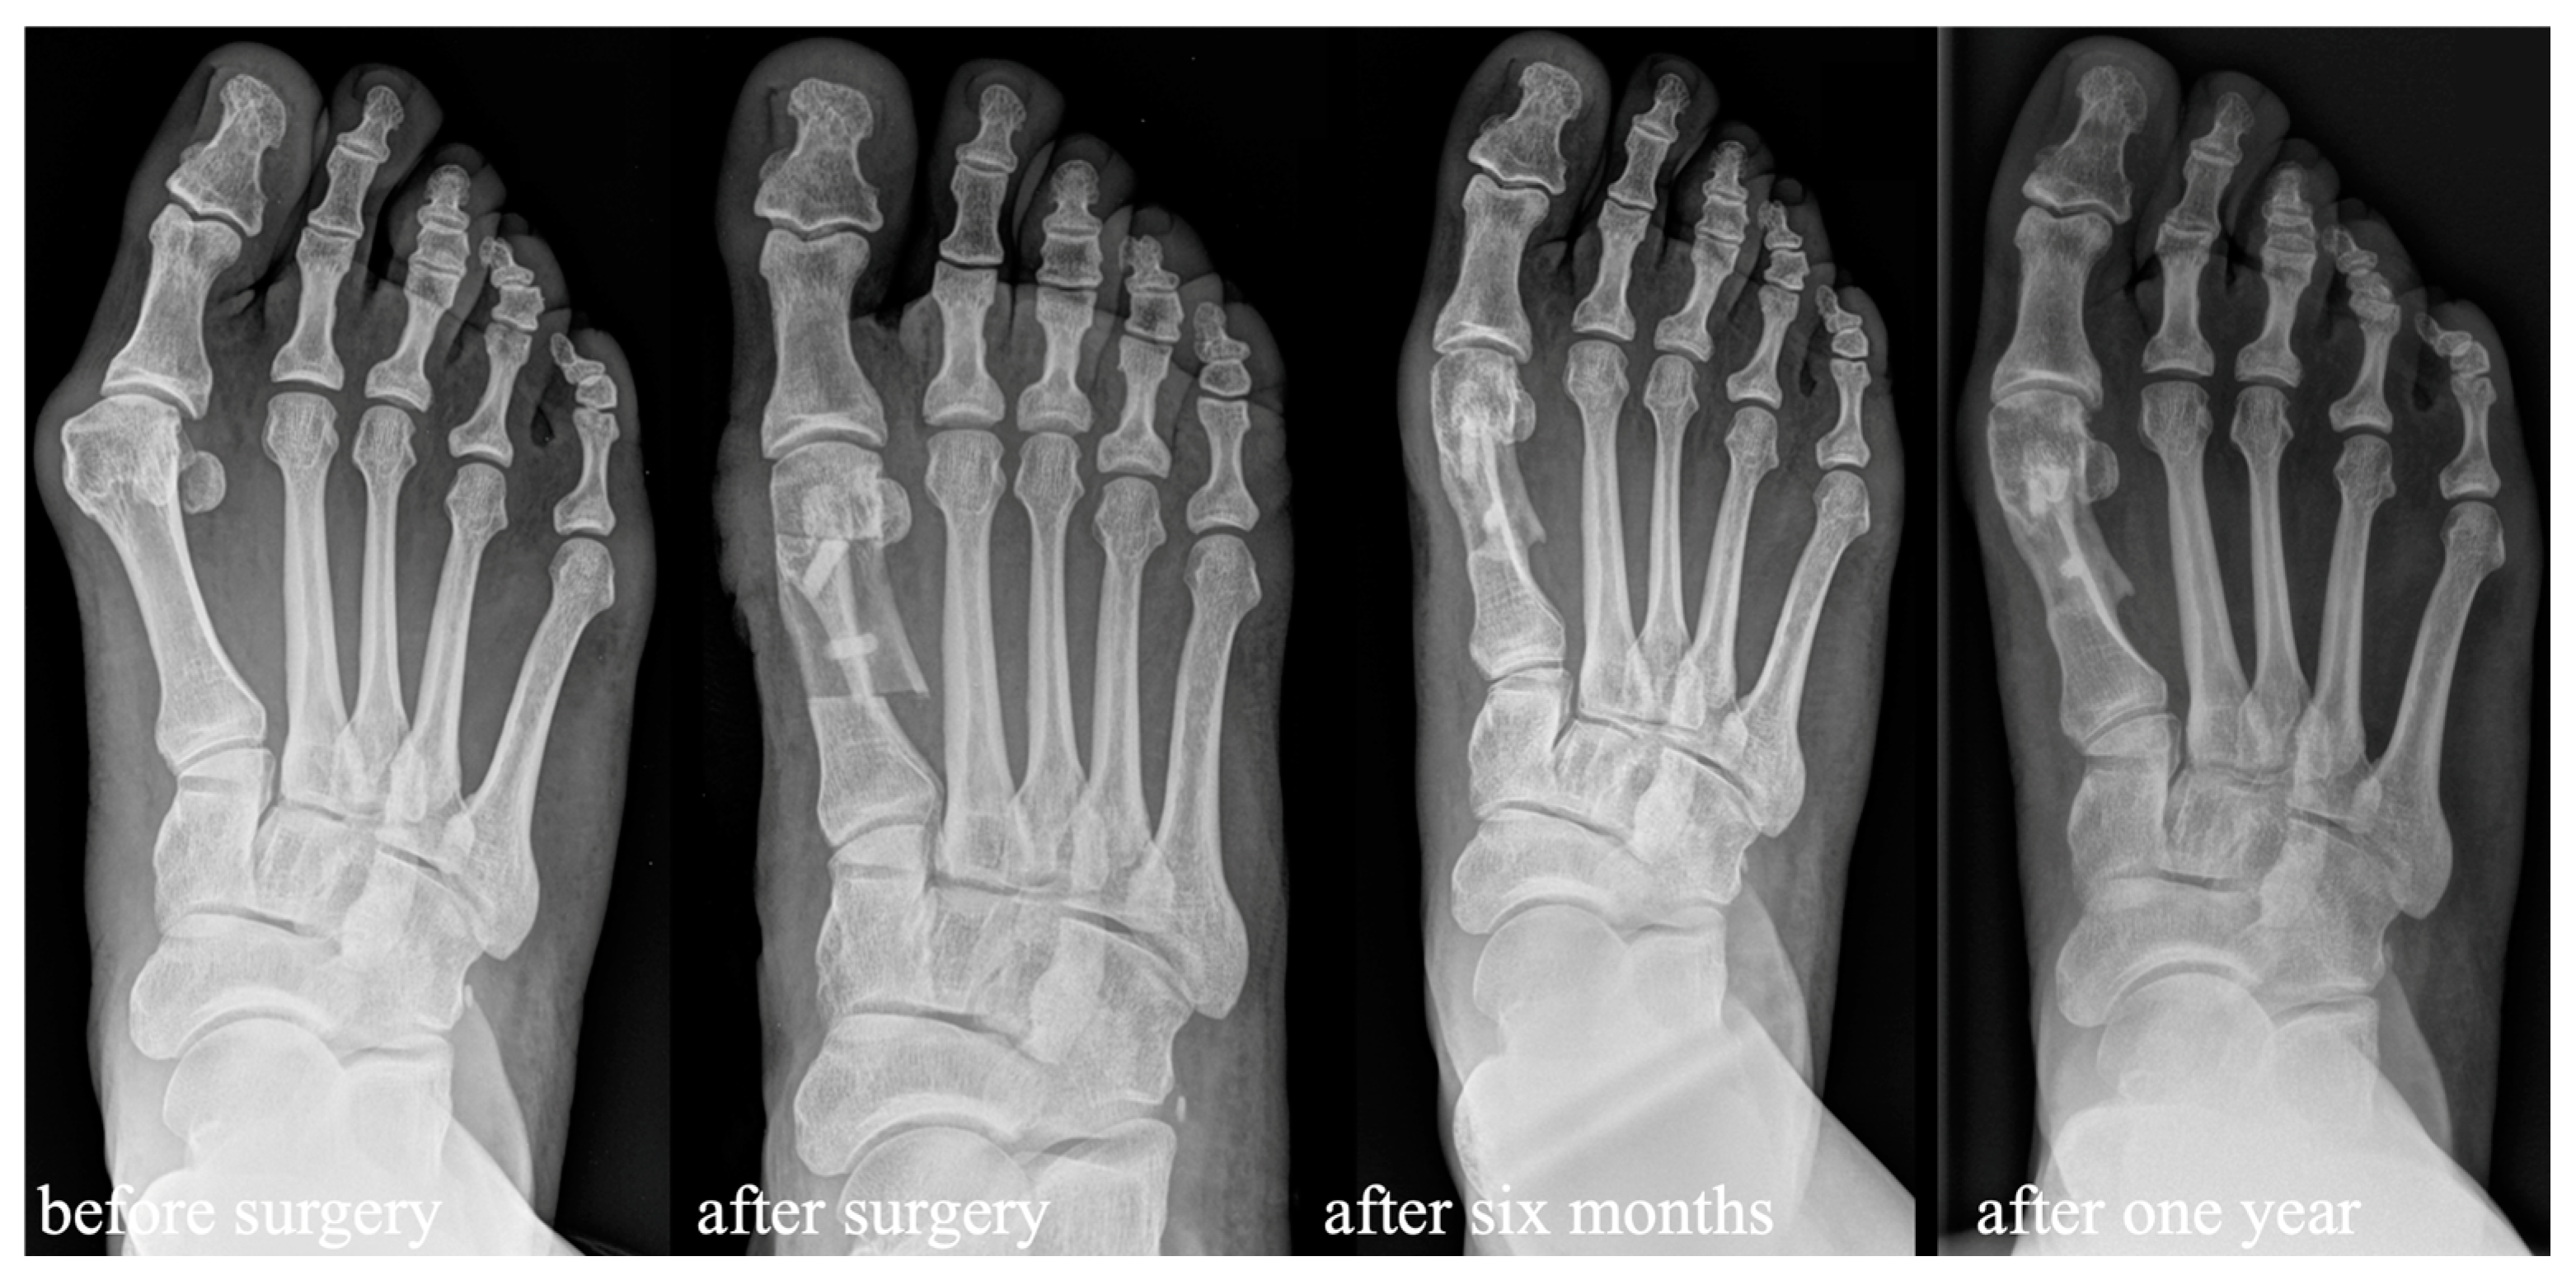

3.2. Comparison of the Usage of Allograft Bone Screws to HCS for Scarf Fixation